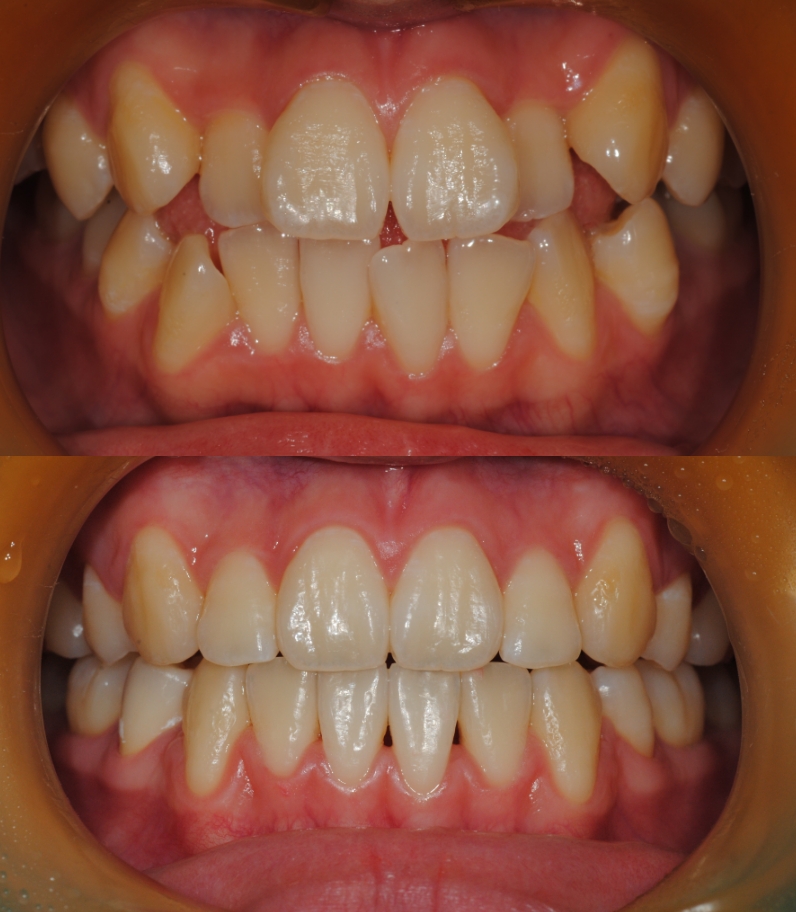

치아교정 전/후

실제 케이스

소아 교정부터 성인 교정까지 환자분들의

상황과 상태에 맞는

올바른 치료를 위해

끊임 없이 연구하고 고민합니다.

치아교정

치료기간 : 2023.05 - 2024.05 (1년)